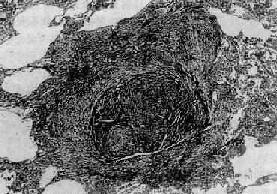

三、职业性肺疾病在职业活动、特别是生产过程中,因长期吸入有害粉尘,引起以肺广泛纤维化为主要病变的疾病,统称尘肺(pneumoconiosis)。尘肺是我国一种法定职业病。属职业性尘肺的病种较多,按粉尘的化学性质可将其分为无机尘肺和有机尘肺两大类。无机尘肺中常见的有硅肺、煤工尘肺、石棉肺等。有机尘肺是因吸入各种有机尘埃,最常见的是由霉菌的代谢产物或动物性蛋白质引起的尘肺,如农民肺、蔗尘肺、蘑菇肺、麦芽肺和饲禽者肺等。尘肺对健康危害极大,关键在于预防。改革不合理的生产过程,建立粉尘监测制度,切实落实综合防尘措施。不接触粉尘或减少吸入粉尘的机会,对于粉尘作业工人定期体检,做到早期检查、早期诊断,对已确诊为尘肺患者及早调离粉尘作业,并进行必要的治疗,完全可以控制和减少尘肺的发病率。 (一)矽肺 矽肺(silicosis)是在生产环境中长期吸入大量含游离二氧化硅(SiO2)粉尘微粒所引起的以肺纤维化为主要病变的全身性疾病。游离二氧化硅主要存在于石英中,石英成分中SiO2占97%~99%。约有70%的矿石中均含有较多的SiO2。长期从事开矿、采石作业、坑道作业以及在石英粉厂、玻璃厂、耐火材料厂、陶瓷厂和搪瓷厂生产作业的工人易患本病。矽肺是危害最严重的一种职业病,其特点是发展缓慢,即使在脱离矽尘作业后,病变仍然继续缓慢发展。患者多在接触矽尘10~15年后才发病。若因吸入高浓度、高游离二氧化硅含量的矽尘,经1~2年后发病者,称速发型矽肺。矽肺的早期即有肺功能损害,但因肺的代偿能力很强,患者往往无症状,随着病变的发展,尤其是合并肺结核和肺心病时,则逐渐出现不同程度的呼吸和心功能障碍。 【病因和发病机制】 游离二氧化硅是矽肺的致病因子。矽肺的发生、发展与矽尘中游离二氧化硅的含量,生产环境中矽尘的浓度、分散度,从事矽尘作业的工龄及机体防御功能等因素有关。矽尘粒子愈小,分散度愈度,在空气中的沉降速度愈慢,被吸入的机会就愈多,致病作用亦愈强。一般来说,大于5μm的矽尘往往被阻留在上呼吸道,并可被呼吸道的防御装置清除。小于5μm的矽尘才能被吸入肺泡,并进入肺泡间隔,引起病变。尤以1~2μm的矽尘微粒引起的病变最为严重。 吸入肺泡内的矽尘微粒被肺巨噬细胞吞噬,沿肺淋巴流经细支气管周围、小血管周围、小叶间隔和胸膜再到达肺门淋巴结。当淋巴道阻塞后,矽尘沉积于肺间质内引起矽肺病变。若局部沉积的矽尘量多,引起肺巨噬细胞局灶性聚积,可导致矽结节形成;若矽尘散在分布,则引起弥漫性肺间质纤维化。矽肺的发病机制尚未完全阐明。一般认为,矽尘被肺巨噬细胞吞噬后,在游离二氧化硅的毒性作用下,巨噬细胞大量死亡崩解或发生功能和生物学行为改变,释放出一些致纤维化因子、包括巨噬细胞生长因子(MDGF),白细胞介素Ⅰ(IL-1)和纤维连结蛋白(FN)等,促进成纤维细胞增生和胶原形成,导致纤维化。至于巨噬细胞死亡的原因,主要是由于矽尘被巨噬细胞吞噬后,存在于次级溶酶体中,矽尘表层中的SiO2逐渐与水聚合成硅酸(系一种强的成氢键化合物),其羟基基团与溶酶体膜脂蛋白结构上的受氢原子(氧、氮或硫)间形成氢键,改变了溶酶体膜的脂质分子构型,从而破坏了膜的稳定性或完整性。溶酶体膜通透性增高或破裂,其中所含的大量水解酶溢出到细胞内,导致巨噬细胞自溶崩解。巨噬细胞死亡崩解后,释出的矽尘又被其它巨噬细胞吞噬,如此反复进行,使病变不断发展、加重。这也可解释何以患者脱离矽尘作业后肺部病变仍然会继续发展的缘由。 随着免疫学的发展,大量关于矽肺免疫的研究表明,在矽肺发生、发展过程中,有免疫因素参与。根据对矽结节玻璃样变组织的生化分析,其中球蛋白含量明显高于胶原含量,而有别于一般的玻璃样变组织的成分。动物实验证明,矽肺病变的纤维化程度与浆细胞反应强度呈正相关,提示矽肺的纤维化与抗原抗体反应有关。用荧光免疫组织化学方法观察矽结节,发现在胶原纤维及其间隙中有大量γ-球蛋白沉积,主要是IgG和IgM。如将尸检取得的矽结节玻璃样变组织制成匀浆,给家兔注射后,能产生抗人γ-球蛋白抗体。有人认为,浆细胞产生的免疫球蛋白通过形成抗原抗体复合物参与矽肺的发病。对矽肺患者作体液免疫测定发现,血清中IgG和IgM浓度增高,抗肺自身抗体、抗核抗体和类风湿因子检出率也较高。但关于矽肺免疫的抗原物质目前还未提取出来,多认为有3种可能性:①矽尘作为半抗原与机体的蛋白质结合构成复合抗原;②矽尘表面吸附的γ-球蛋白转化为自身抗原;③矽尘导致巨噬细胞死亡崩解后释放自身抗原。现已有很多证据表明,巨噬细胞死亡崩解后释放抗原的可能性最大。总之,矽肺的病因是明确的,发病机制极为复杂,在发病过程中可能有多种因素参与,它们互相影响、互为因果,共同促进矽肺的发生和发展。 【病理变化】 矽肺的基本病变是肺组织内矽结节形成和弥漫性间质纤维化。矽结节是矽肺的特征性病变,结节境界清楚,直径2~5mm,呈圆形或椭圆形,灰白色,质硬,触之有砂样感。随着病变的发展,结节可融合成团块状,在团块的中央,由于缺血、缺氧而发生坏死、液化,形成矽肺性空洞(silicotic cavity)。矽结节的形成过程大致分为三个阶段:①细胞性结节,由吞噬矽尘的巨噬结胞局灶性聚积而成,巨噬细胞间有网状纤维,这是早期的矽结节;②纤维性结节,由纤维母细胞、纤维细胞和胶原纤维构成;③玻璃样结节,玻璃样变从结节中央开始,逐渐向周围发展,往往在发生玻璃样变的结节周围又有新的纤维组织包绕。镜下,典型的矽结节是由呈同心圆状或旋涡状排列的、已发生玻璃样变的胶原纤维构成(图9-22)。结节中央往往可见内膜增厚的血管。用偏光显微镜观察,可以发现沉积在矽结节和肺组织内呈双屈光性的矽尘微粒。除矽结节外,肺内还有不同程度的弥漫性间质纤维化(图9-23),范围可达全肺2/3以上。此外,胸膜也因纤维组织弥漫增生而广泛增厚,在胸壁上也可形成胸膜胼胝,甚至可厚达1~2cm。肺门淋巴结内也有矽结节形成和弥漫性纤维化及钙化,淋巴结因而肿大、变硬。

图9-22 矽肺 矽结节,由呈旋涡状排列的已发生玻璃样变的胶原纤维构成